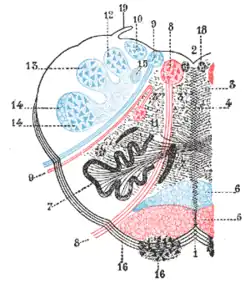

Ort der Schädigung

Schäden des Nucleus spinalis nervi trigemini verursachen das Fehlen von Schmerzen auf der ipsilateralen Seite des Gesichtes, genau wie einen abgeschwächten oder fehlenden Cornealreflex. Ist der Tractus spinothalamicus geschädigt, dann kommt es zum Fehlen der Schmerz- und Temperaturwahrnehmung auf der dem Infarkt gegenüberliegenden Seite des Körpers. Der Schaden im Kleinhirn oder/und im unteren Kleinhirnschenkel (Pedunculus cerebellaris inferior) führt zur Ataxie. Durch den Schaden in den hypothalamospinalen Fasern wird die sympathische Signalübertragung gestört, und es kann zum Horner-Syndrom kommen. Augenzittern und Schwindel werden durch die Beteiligung der Region des Nucleus Deiter (Nucleus vestibularis lateralis) und anderer vestibulärer Kerne verursacht. Ein palataler Myoklonus kann eventuell bei einer Störung des Tractus tegmentalis centralis vorkommen.